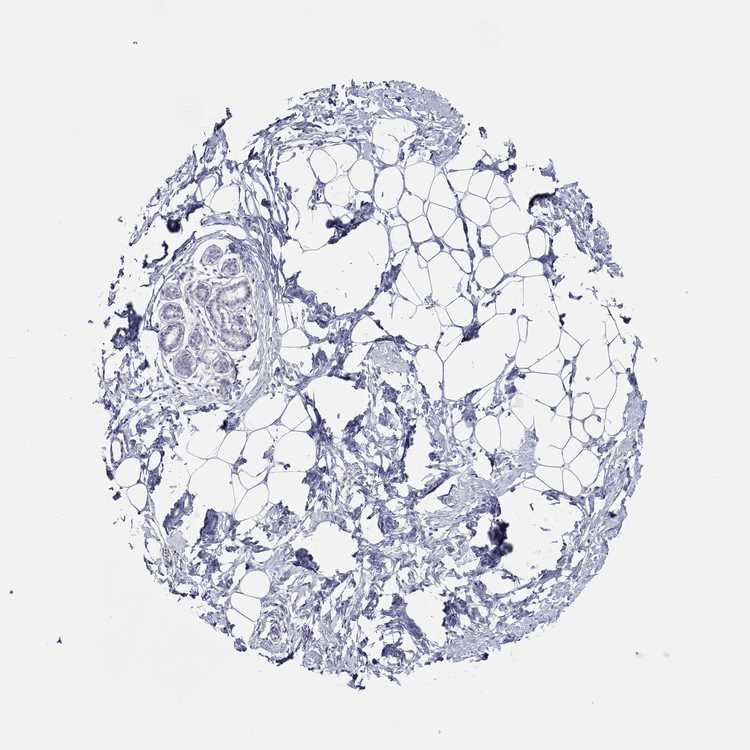

TISSUE PRIMARY DATA BREAST Show tissue menu

Breast

BREAST - Antibody stainingi

Antibody staining in the annotated cell types in the current human tissue is reported as not detected, low, medium, or high, based on conventional immunohistochemistry profiling in selected tissues. This score is based on the combination of the staining intensity and fraction of stained cells.

Each image is clickable and will lead to virtual microscopy that enables deeper exploration of all samples and also displays staining intensity scores, fraction scores and subcellular localization as well as patient and tissue information for each sample.

Antibody HPA036313Antibody HPA052147

Adipocytes Not detectedNot detected

Glandular cells Not detectedNot detected

Myoepithelial cells Not detectedNot detected